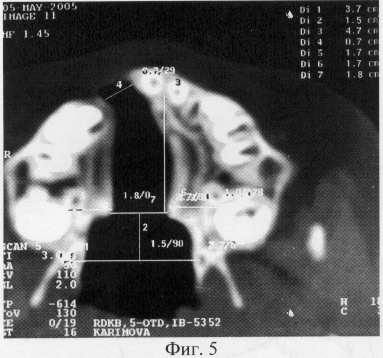

На фиг.1 представлена фотография костей твердого неба в норме; на фиг.2 изображена схема уровня среза черепа в аксиальной проекции под углом, соответствующим пунктирной линии; на фиг.3 изображена схема горизонтальной плоскости твердого неба и крючков крыловидных отростков клиновидной кости с проведенными измерениями; на фиг.4 представлена боковая топограмма черепа с отмеченным линией уровнем среза; на фиг.5 представлена томограмма горизонтальной плоскости твердого неба и крючков крыловидных отростков клиновидной кости с проведенными планиметрическими измерениями.

После клинического обследования выполнена боковая топограмма черепа и определен уровень среза (фиг.4). Затем проведено сканирование и планиметрические исследования (фиг.5): ширина расщелины на уровне альвеолярного отростка 7 мм, на уровне задневнутренних углов фрагментов горизонтальной пластинки небной кости 18 мм; ширина собственно фрагментов небных пластинок на уровне задневнутренних углов – 17 мм справа и 17 мм слева; фактическая длина горизонтальной плоскости твердого неба составила 47 мм, а фактическая величина укорочения твердого неба составила 15 мм. Вычислен индекс укорочения: (15:47)×100=31,9%.